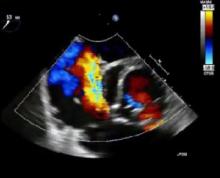

This video demonstrates a "hemi-commando" procedure in a 64-year-old female patient with aortic root abscess involving the intervalvular fibrosa. The hemi-commando procedure is a feasible treatment option for invasive double-valve endocarditis, and has the advantage of mitral valve preservation.